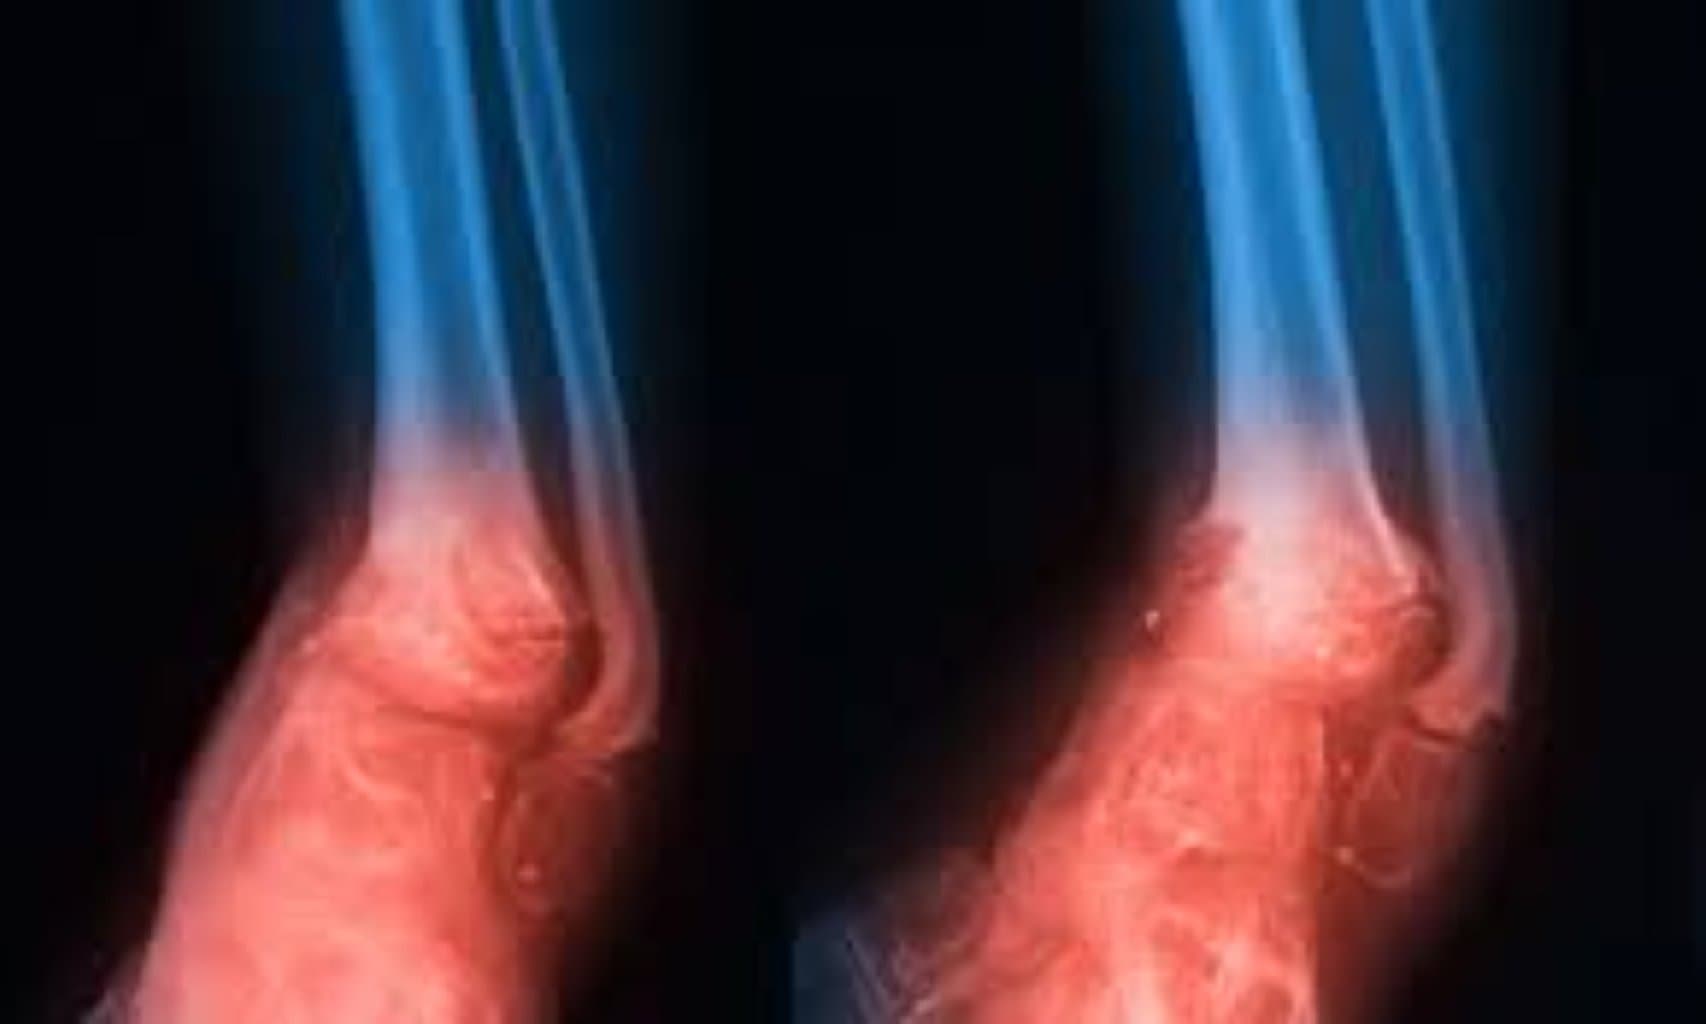

Osteomielit müalicəsi, sümük toxumasında yaranan infeksiyanın aradan qaldırılması və sümük strukturunun qorunması məqsədilə tətbiq edilən kompleks tibbi prosedurlardır. Bu ciddi sağlamlıq probleminin idarə olunmasında xəstənin vəziyyətinə uyğun olaraq həm konservativ, həm də cərrahi metodlardan istifadə edilir. Müalicənin effektivliyi infeksiyanın növündən və yayılma dərəcəsindən birbaşa asılıdır.

Əgər konservativ üsullar infeksiyanı kontrol altına almaqda yetərsiz qalarsa və ya sümükdə ağır fəsadlar yaranarsa, cərrahi müdaxilə zərurətə çevrilir. Xüsusilə irin birikməsi, nekrotik toxuma (ölü toxuma) və ya ciddi sümük zədələnmələri zamanı cərrahiyyə qaçılmazdır.